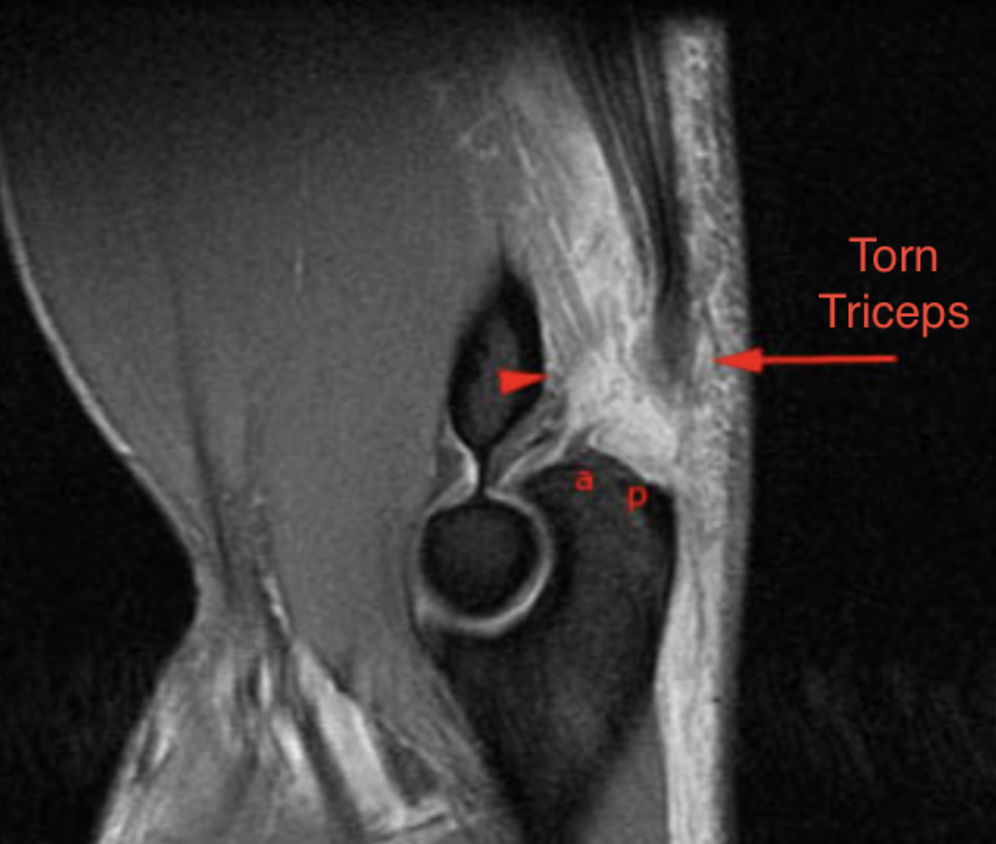

- MRI: Confirmatory — shows the level of disruption, degree of retraction, and whether repair is feasible. Partial tears can be distinguished from complete ruptures.